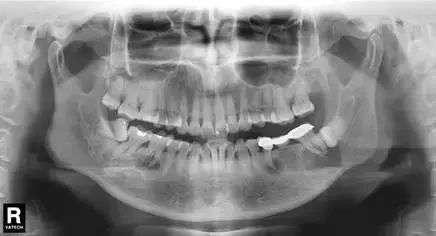

这里要特别强调一下全景片,建议每个人一生要至少为自己的牙齿拍一张全景片——

通过全景片不仅能了解“牙齿”本身的病变情况,还可以了解“牙根”下有没有囊肿、周围骨头有没有吸收 以及 牙槽骨内是否有“埋伏牙”、“多生牙”等 其它外观不能看见的病灶。